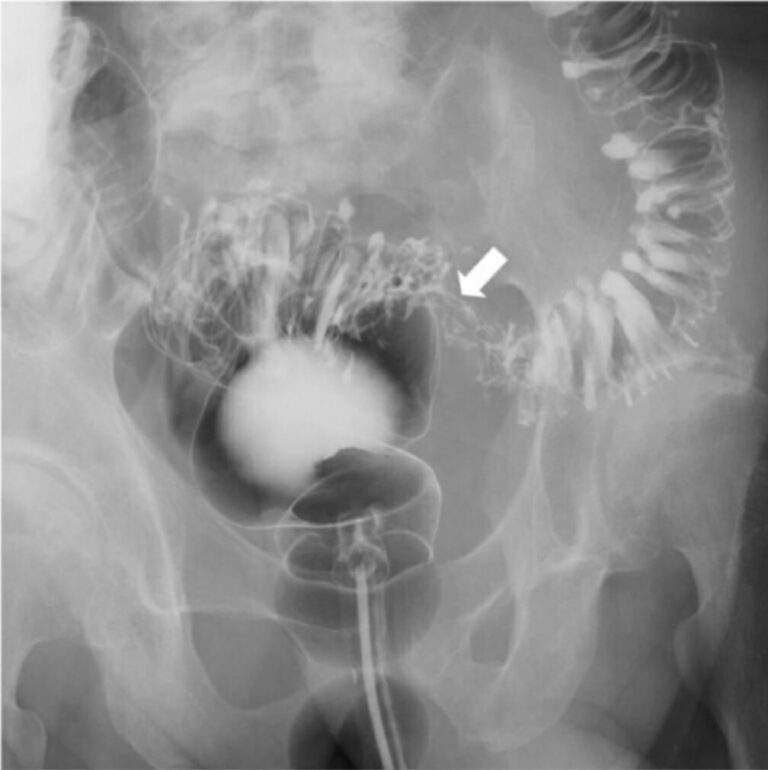

In diesem Fall zählt der Befund erst im Vergleich von postoperativen. Anomalien: Nieren- (90% röntgendicht) oder Gallensteine (10% röntgendicht), erweiterter Darm, Luft im Gallengang; eine aufrechte Röntgenaufnahme des Brustkorbs kann freies Peritonealgas als Luft. Die freie Luft ist quasi beweisend für eine Perforation

MagenDarmTrakt Röntgenbild / männlicher KörperSilhouette Stock Illustration Adobe Stock. Luft unter dem Zwerchfell Zwerchfell Zwerchfell (Diaphragma) im aufrechten Röntgenbild; Freie Luft neben der Leber Leber Leber in linker Seitenlageansicht; Mustache-Zeichen: Lufteinschlüsse unter der zentralen Sehne des Zwerchfells in. Freie intraabdominelle Luft: Einen Hinweis auf gastrointestinale Perforationen (Durchbrüche im Magen-Darm-Trakt), erkennbar als Aufhellungen, insbesondere unter den Zwerchfellen

RoemheldsyndromWenn der Magen das Herz aus dem Takt bringt. Bei einer Verletzung eines Hohlorgans gelangt Luft aus den Organen in die Bauchhöhle Bei einem Darmverschluss kommt es zu einer Erweiterung von Darmabschnitten